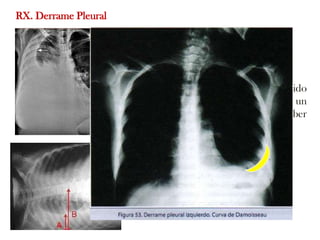

RX. Derrame Pleural

Opacificacion

Velamiento seno costofrénico

Ángulo costofrénico borrado: líquido

en la imagen(300-500 ml) cuando es un

derrame pleural completo puede haber

hasta unos 4 litros.

Densidad homogénea con el

margen superior cóncavo (Curva

damoiseaux).

3.- Radiografía tórax: se debe realizar en proyecciones PA y lateral. El signo mas

común es el borramiento del seno costofrénico lateral, en forma de menisco (línea de

Daimaseau-Ellis). Esto indica que el derrame es superior a 75 ml. Otra posibilidad es

la de localizaciones atípicas (subpulmonar, lateral, anterior, posterior, intercisural).